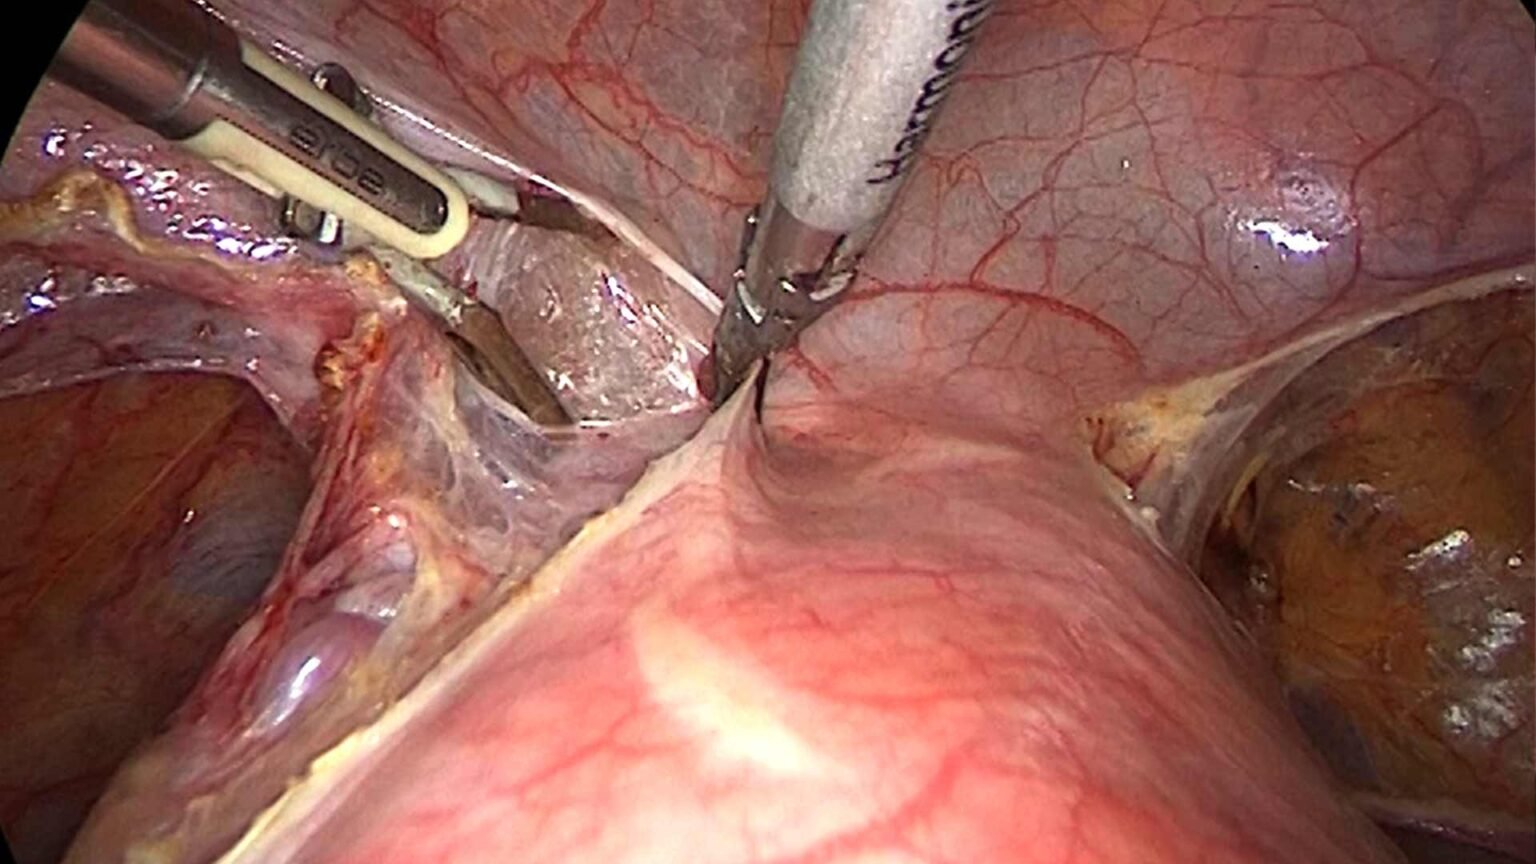

Uno dei principali vantaggi della chirurgia laparoscopica è la migliore visualizzazione dei dettagli anatomici offerta dalle ottiche di ultima generazione in alta definizione. Questo permette ai chirurghi di avere una visione chiara e dettagliata dell’area operativa, consentendo una maggiore precisione nei movimenti e una migliore identificazione delle strutture anatomiche coinvolte.

Inoltre, l’utilizzo di ottiche in 3D consente una percezione tridimensionale dell’area operativa, migliorando ulteriormente la precisione e facilitando la navigazione attraverso i tessuti. Questo contribuisce a una maggiore sicurezza durante l’intervento e una migliore identificazione delle piccole strutture anatomiche.

La chirurgia laparoscopica offre anche numerosi benefici post-operatori. Grazie all’utilizzo di incisioni cutanee piccole, i pazienti sperimentano un minor trauma chirurgico, un minor sanguinamento e una riduzione del dolore post-operatorio.